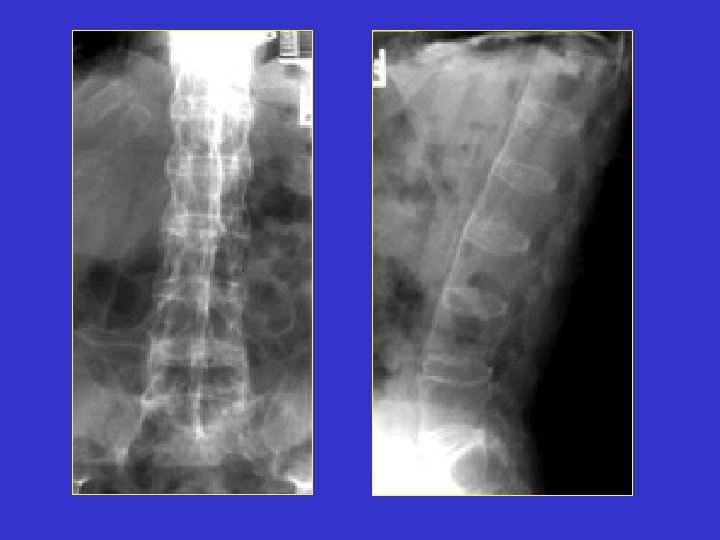

BAMBOO SPINE

Diagnosis: Ankylosing Spondylitis Discussion: Anterior and lateral radiograph of the lumbar spine which reveals near complete fusion of all of the vertebral bodies. Spinal changes which include squaring of the vertebral bodies and fusion between adjacent levels. The fusion is secondary to syndesmophytes and resembles a bamboo stalk. This is most commonly found in ankylosing spondylitis